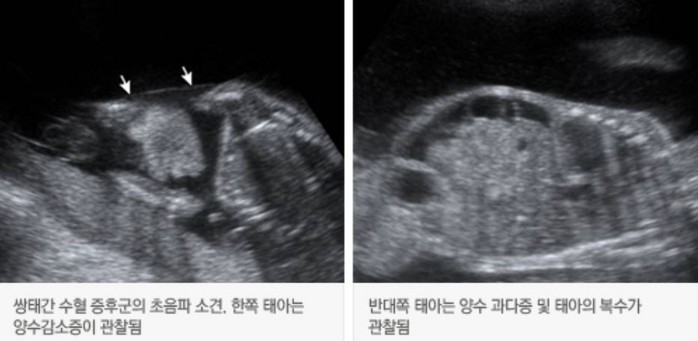

| ▲삼성서울병원 제공 |